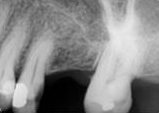

antes depois